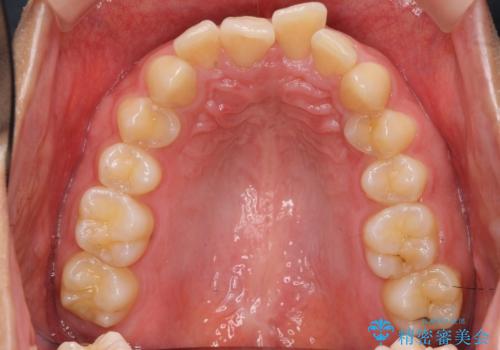

深いかみ合わせ 出っ歯の治療 インビザラインで

- 前歯の前突を主訴に来院。

かみ合わせが深く、また奥歯のかみ合わせも全体的に上が前にずれていました。

抜歯矯正も難しく、非抜歯矯正も歯の移動量が多くいずれにしても難易度が高い状態でした。

時間はかかりますが非抜歯で治療することにして、インビザライン矯正とワイヤー矯正を交互に行い仕上げました。

インビザライン矯正だけでなく、途中ワイヤー矯正もはさみました。前歯のかみ合わせが深く、本当に大変な治療でしたが協力度も高く非抜歯で上の奥歯を後ろに動かすことができました。